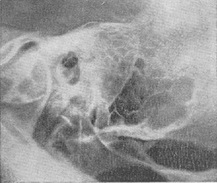

Вогнище деструкції кісткової може мати деякий час трабекулярное будова через збережених клітин, що оточують порожнину абсцесу. Томографія скроневої кістки дозволяє виявити в цій фазі гнійник. При утворенні субпериостального абсцесу з повним руйнуванням кістки виникає інтенсивне гомогенне просвітлення (рис. 2 і 3). Велика солітарна клітка в сосцевидном відростку - відносно рідкісний анатомічний варіант (рис. 4 і 5) - при гострому отиті може вести до неправильної рентгенодіагностиці мастоидита, особливо його латентної форми, при бідному клітинами сосцевидном відростку. Порожнину такий клітини помилково приймається навіть за холестеатому (рис. 6), що потрапив у соскоподібний відросток. Наявність периантральных клітин вказує на анатомічний варіант, але не на вушну холестеатому, завжди сполучається з холестеатомной порожниною в антруме.

Для виявлення затемнених периантральных клітин і холестеатомной порожнини в області антрума слід користуватися проекцією Майєра. Порожнину субпериостального абсцесу, якщо вона не утворилася з кількох великих клітин (рис. 7), як правило, не має чітких обрисів, властивих холестеатоме. Верхівковий мастоїдит (абсцес Бецольда) можна не виявити, якщо обмежитися однією лише проекцією Шюллер. Рентгенограма по Стенверсу дозволяє виявити дефект внутрішньої кортикальної пластинки соскоподібного відростка (рис. 8-10).

Рис. 1. Рентгенограма скроневої кістки за Шюллеру; гострий мастоїдит; затемнені клітини, великий деструктивний вогнище в сосцевидном відростку (симптом вторинного просвітлення).

Рис. 2. Гострий мастоїдит, великий кістковий дефект в сосцевидном відростку; субпериостальный абсцес (права скронева кістка). Рис. 3. Ліва скронева кістка (норма) - порівняльна рентгенограма.

Рис. 4 і 5. Рентгенограми нормальної скроневої кістки (рис. 4 - проекція Шюллер; рис. 5 - коса проекція соскоподібного відростка по Стенверсу). Велика солітарна клітина верхівки соскоподібного відростка з тонким лінійним тіньовим контуром. Рис. 6. Порожнину холестеатоми на верхівці відростка з тонким лінійним тіньовим контуром; клітини відсутні (проекція Шюллер).